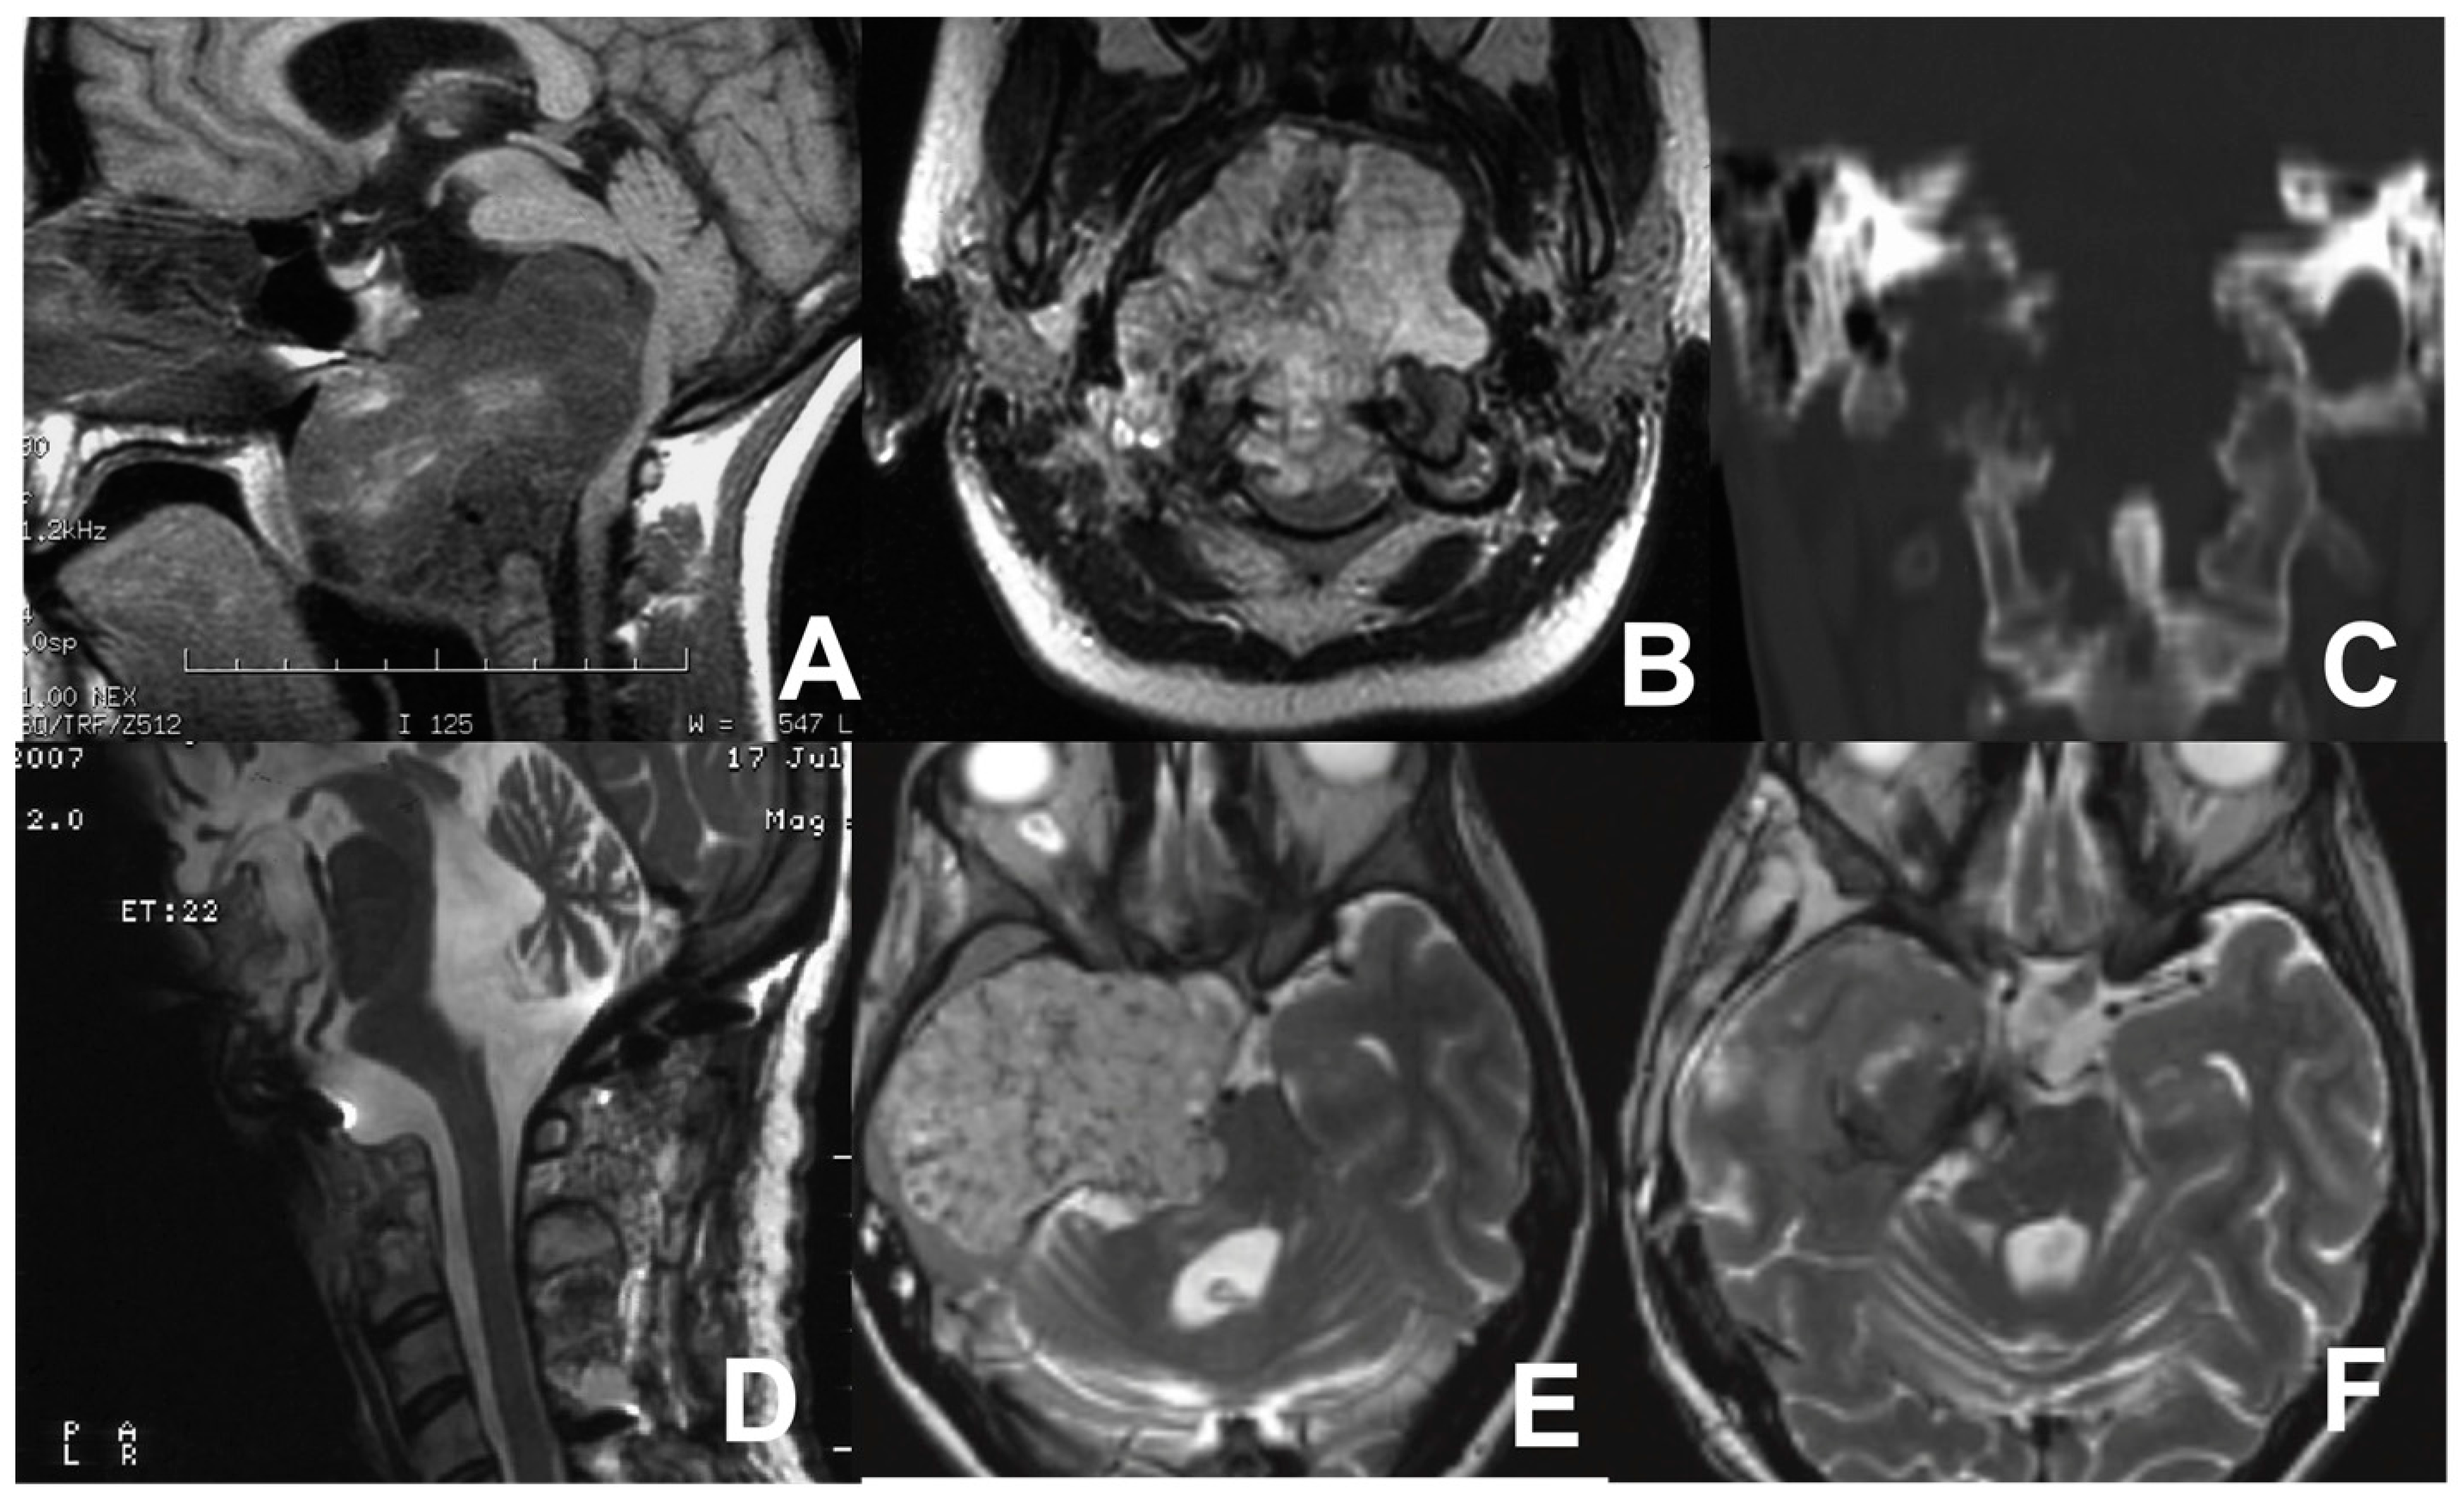

Figure 6.

MRI sagittal (A) and coronal (B) views showing the huge chordoma in the lower third of the clivus, extending to the body of C2, causing posterior displacement of the brainstem, and compressing the nasopharynx. CT scan (C) showing osseous erosion of the occipital condyles, anterior arch of C1, and a portion of the C2 body. Postoperative MR scan after first operation (D). Pre- (E) and postoperative (F) axial MRI scans after the tumor relapse involving the clivus, sphenoid region, right petrous bone, and temporal fossa with severe compression of the brainstem.

A two-stage surgical procedure was performed, employing subtemporal/infratemporal and retrosigmoid approaches. The patient underwent extensive tumor resection and decompression of the temporal lobe and brainstem. A remarkable improvement in the patient’s neurological conditions was documented. The closure of the gastrostomy occurred prior to discharge, and the tracheostomy was removed one month later.